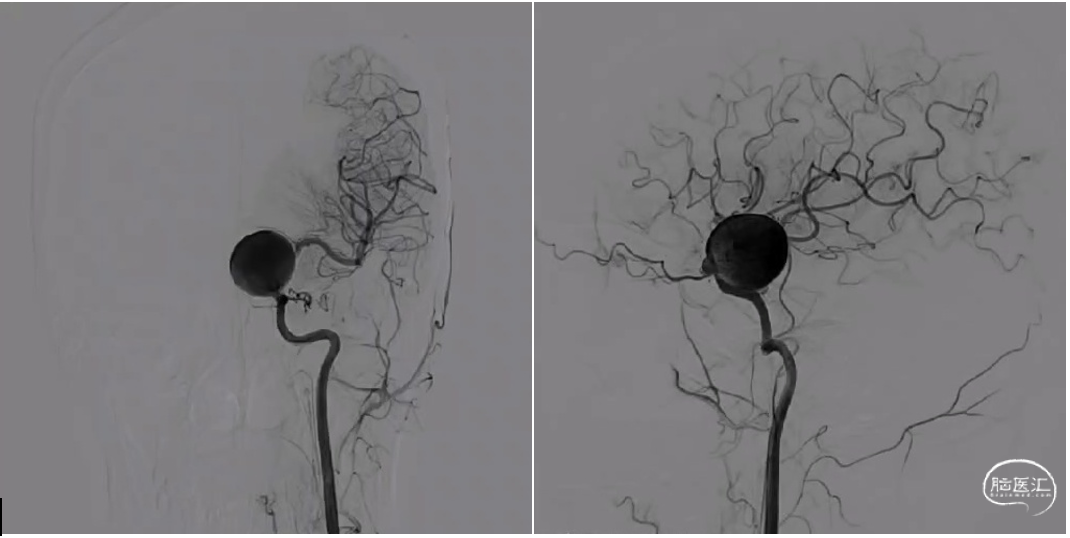

颈内动脉狭窄状况及闭塞试验

1. 术后一周复查DSA显示动脉瘤无血流,桥血管通畅。

2. 术后三个月复查CTA显示动脉瘤无血流,桥血管通畅。